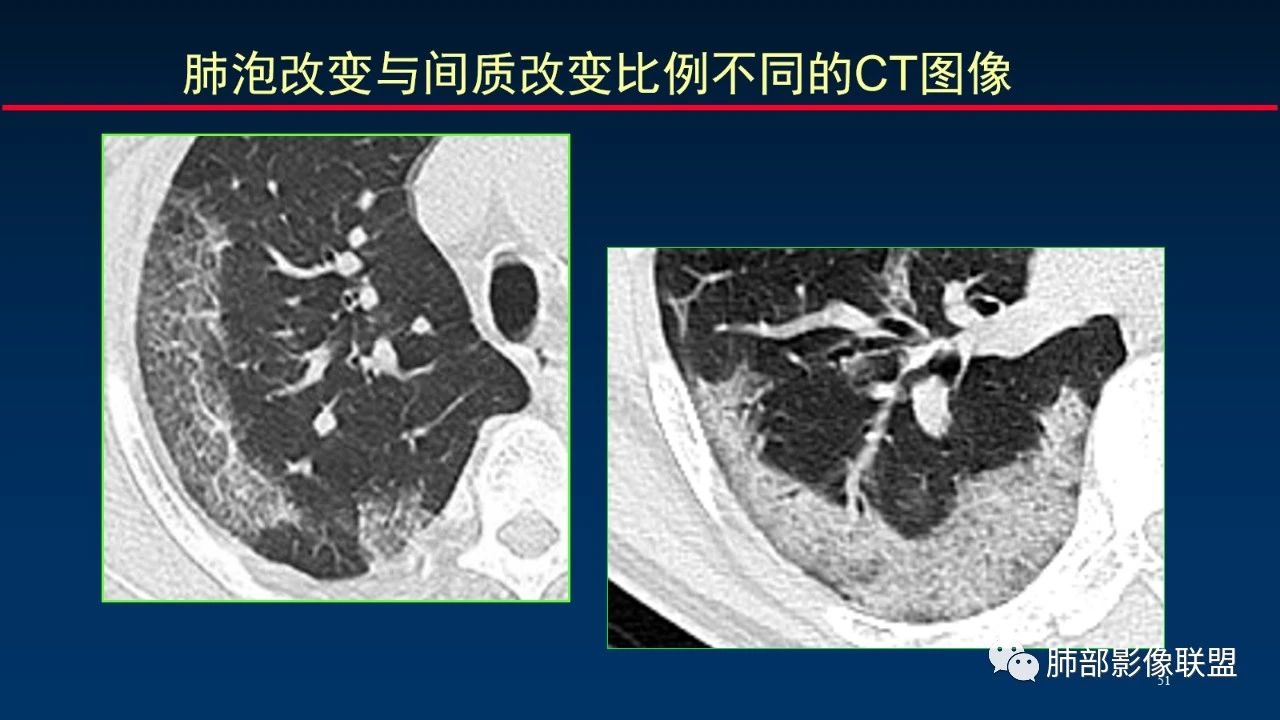

病毒性肺炎是间质性改变为主的肺炎,与CT征象有关的有两个病理特点,即间质改变及肺泡渗出。由于是呼吸道感染所以病灶常常沿支气管走行分布。

(一)肺间质改变:主要是小叶内间质增厚(细网格),气腔相对减小,呈现磨玻璃密度片影和/或结节影,可以发生蜂窝肺。病灶整体边界不清,通常不会出现胸膜下回避。

有时磨玻璃密度区可呈现充血增粗肺血管影。

(二)肺泡渗出:依气腔填塞程度,轻则单纯磨玻璃密度,重则实变,或两者混杂出现。很少有边界清楚的梅花瓣样轮廓或胸膜牵拉凹陷。